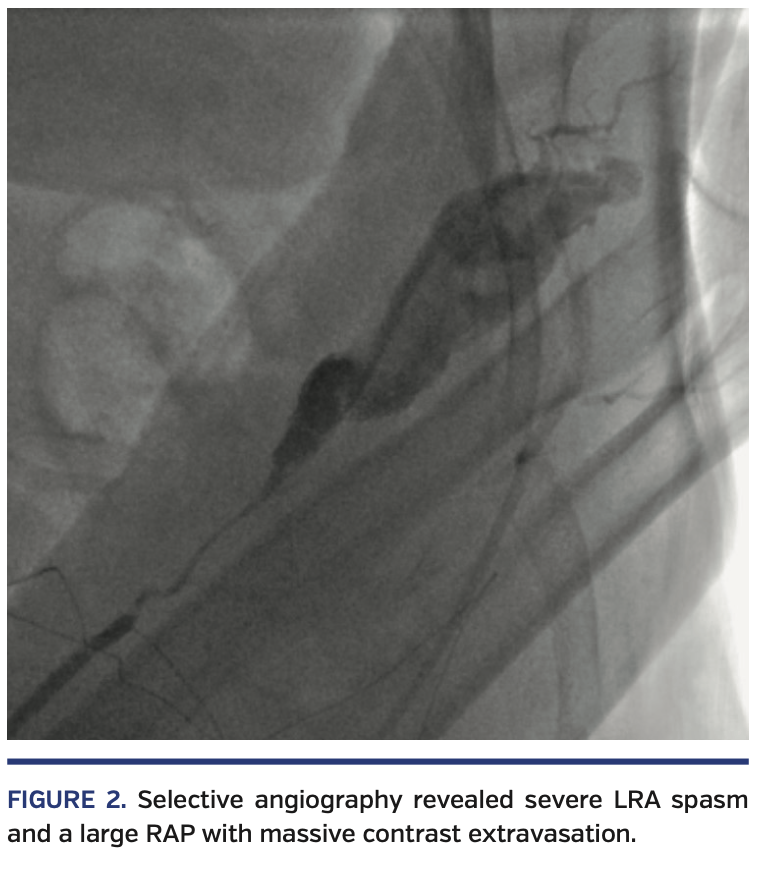

A 62-year-old woman with short stature, hypertension, diabetes, obesity, peripheral arterial disease, and previous acute myocardial infarction (AMI) requiring percutaneous coronary intervention (PCI) of the left anterior descending artery presented with non-ST elevation AMI. She was referred to urgent coronary angiography via left dTRA, using a 5/6 Fr hydrophilic slender Glidesheath (Terumo) inserted without any difficulties (Figure 1). Despite intra-arterial nitroglycerin, resistance was felt at the level of the forearm left radial artery (LRA), and it was not possible to further advance even a hydrophilic 0.035˝ J-tip wire through the LRA. Selective angiography (through the sheath) revealed severe LRA spasm and a large RAP with massive contrast extravasation (Figure 2; Video 1). The wire-crossing attempts always resulted in the false lumen; it was therefore decided to cross the site of perforation with a 5 Fr MP diagnostic catheter, without the rail of a wire, by gentle rotations and advancements. By confirming the normal arterial waveform pressure just proximal to the perforated area, the system was then carefully advanced up to the aortic root. The dominant right coronary artery (RCA) was diffusely diseased, with proximal-mid critical stenosis and a consequent Thrombolysis in Myocardial Infarction 2 flow (Video 2), without any significant lesions at the left coronary. The culprit RCA was promptly fixed by PCI with 3 drug-eluting stents (distal to ostial), requiring adequate pre- and postdilations and laborious reversion of an adenosine refractory no-reflow with papaverine (Video 3). By withdrawing the JR4 6 Fr guiding catheter, a final angiogram confirmed the perforation had been completely sealed without any residual contrast extravasation (Figure 3; Video 4). The patient was monitored for any signs of forearm compromise and uneventfully discharged home 2 days later.